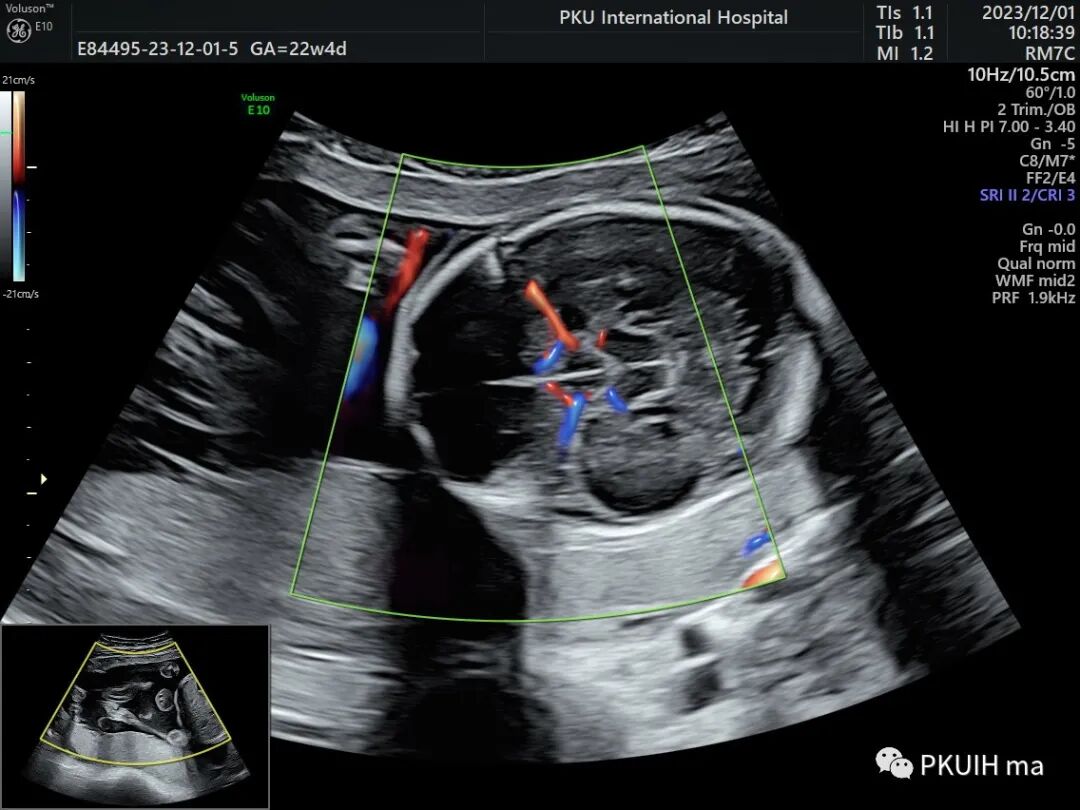

同样用这个功能我们可以很好显示胎儿胼胝体动脉及其分支,效果非常好,对于鉴别胼胝体发育有很大帮助。

另外我们可以采用各种渲染模式来显示胎儿大脑前动脉、胼周动脉及分支